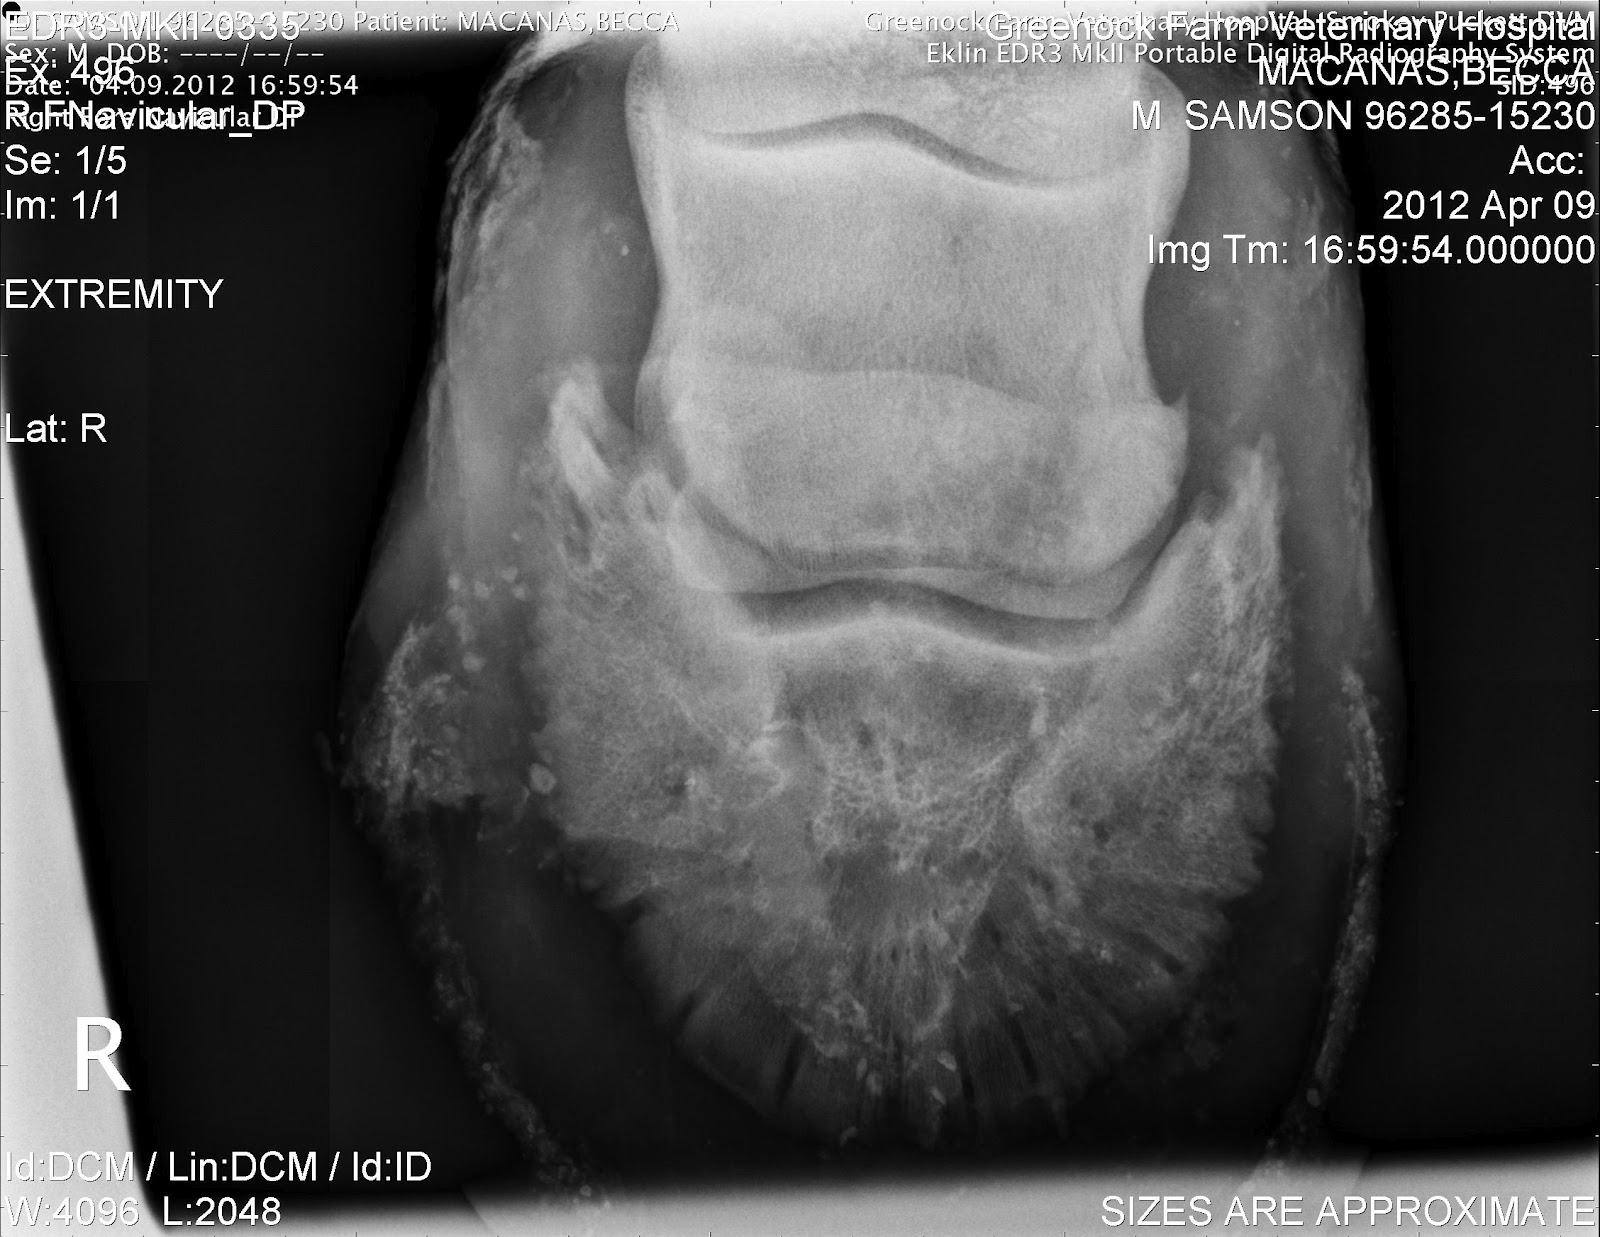

Horse Navicular X Ray . radiographs (x rays) are still important for examining the hoof’s bony structures and changes that are occurring. accurate radiographic evaluation of the navicular bone depends on a radiograph that is properly positioned and exposed and on a foot that is free of distracting artifacts. Many horses have pain in the heel region, which can be elicited by hoof testers. Radiographs will show any degenerative. However, researchers have found in. Abnormalities in the navicular bone navicular in horses relates to problems associated with the navicular bone in the horse’s hoof and is a common diagnosis for lameness in the front foot. Proper preparation for navicular radiography is similar to that for the distal phalanx, as discussed in chapter 23. a study looking at 72 horses that underwent mri for recent onset of navicular syndrome but without abnormalities detected on radiographs found the following: diagnostics involved in determining whether a horse has navicular syndrome include: Most horses show marked improvement in lameness with a palmar digital nerve block.

diagnostics involved in determining whether a horse has navicular syndrome include: radiographs (x rays) are still important for examining the hoof’s bony structures and changes that are occurring. navicular in horses relates to problems associated with the navicular bone in the horse’s hoof and is a common diagnosis for lameness in the front foot. Most horses show marked improvement in lameness with a palmar digital nerve block. Radiographs will show any degenerative. accurate radiographic evaluation of the navicular bone depends on a radiograph that is properly positioned and exposed and on a foot that is free of distracting artifacts. Abnormalities in the navicular bone Many horses have pain in the heel region, which can be elicited by hoof testers. However, researchers have found in. Proper preparation for navicular radiography is similar to that for the distal phalanx, as discussed in chapter 23.